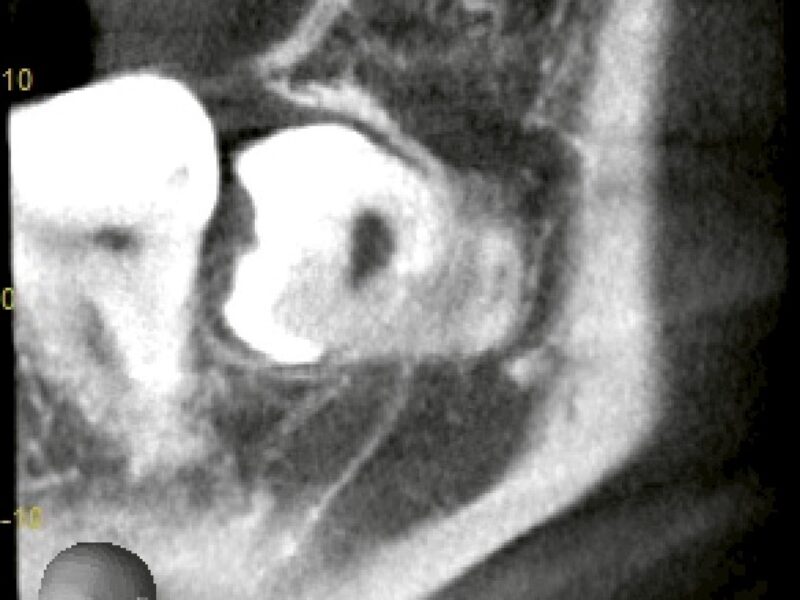

特徴4高精度診断を可能にする「歯科用CT」 -